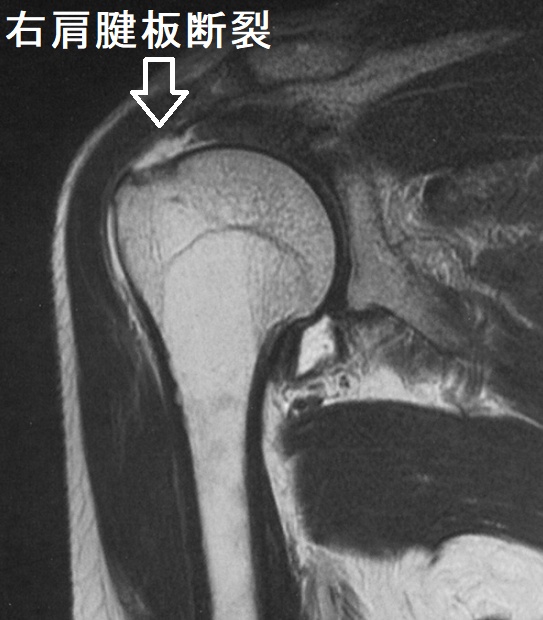

中高年に好発する肩腱板断裂は、重いものを持ち上げた時などに発症。突然の肩痛で始まり、最初は動作時の痛み(動作時痛)、次第に安静時痛と夜間痛も出現します。ある一定の肢位で疼痛が増強する有痛弧徴候、その肢位を保持できない腕落下徴候を認めます。

近年、肩腱板断裂の発生率が増加しています。当然ながら、肩腱板腱には甲状腺ホルモン受容体が存在し、腱の代謝と維持に関与しています。肩腱板断裂で関節鏡手術や小開放手術を受けた患者は、男女ともに高頻度で甲状腺疾患を持っていたとする報告があります。(Muscles Ligaments Tendons J. 2014 Nov 17;4(3):309-14.)

| 年齢(歳) | 女性(%) | 男性(%) |

|---|---|---|

| 20–40 | 50.00 | 14.81 |

| 40–60 | 56.44 | 19.3 |

| 60–80 | 63.6 | 22.67 |

| 80-90 | 27.27 | 0.00 |